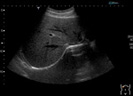

<肝臓>